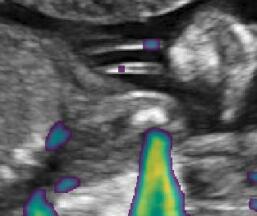

Fig. 6 compares the shadow confidence maps of the state-of-the-art methods and the proposed methods. RW and have the same parameters as used for Table I. The shadow confidence maps of the baseline, the proposed method and the proposedAG method are generated directly from input shadow images by confidence estimation networks. Overall, the proposed method and the proposedAG method achieve more visually reasonable shadow confidence estimation than the baseline and the state-of-the-art on different anatomical structures shown in Fig. 6. The proposed method and the proposedAG method are able to highlight multiple shadow regions while the RW algorithm shows limitations for most cases, especially for disjoint shadow regions.

Row I in Fig. 6 shows a fetal brain image from . The confidence estimation of shadow regions from the baseline, the proposed method and the proposedAG method are similarly accurate since we use fetal brain images to train the confidence estimation networks in these three methods. These outperform [16] and [22]. Rows (II-IV) in Fig. 6 show shadow confidence maps of non-brain anatomy from , including lips, abdominal and cardiac. The baseline failed on unseen data during inference. However, the proposed methods are able to generate accurate shadow confidence maps because of the generalized shadow features obtained by the shadow-seg module. Furthermore, the “Lips” example shows that our method is capable of detecting weaker shadow regions that have not been annotated in manual segmentation. This indicates that the confidence estimation network has learned general properties of shadow regions.